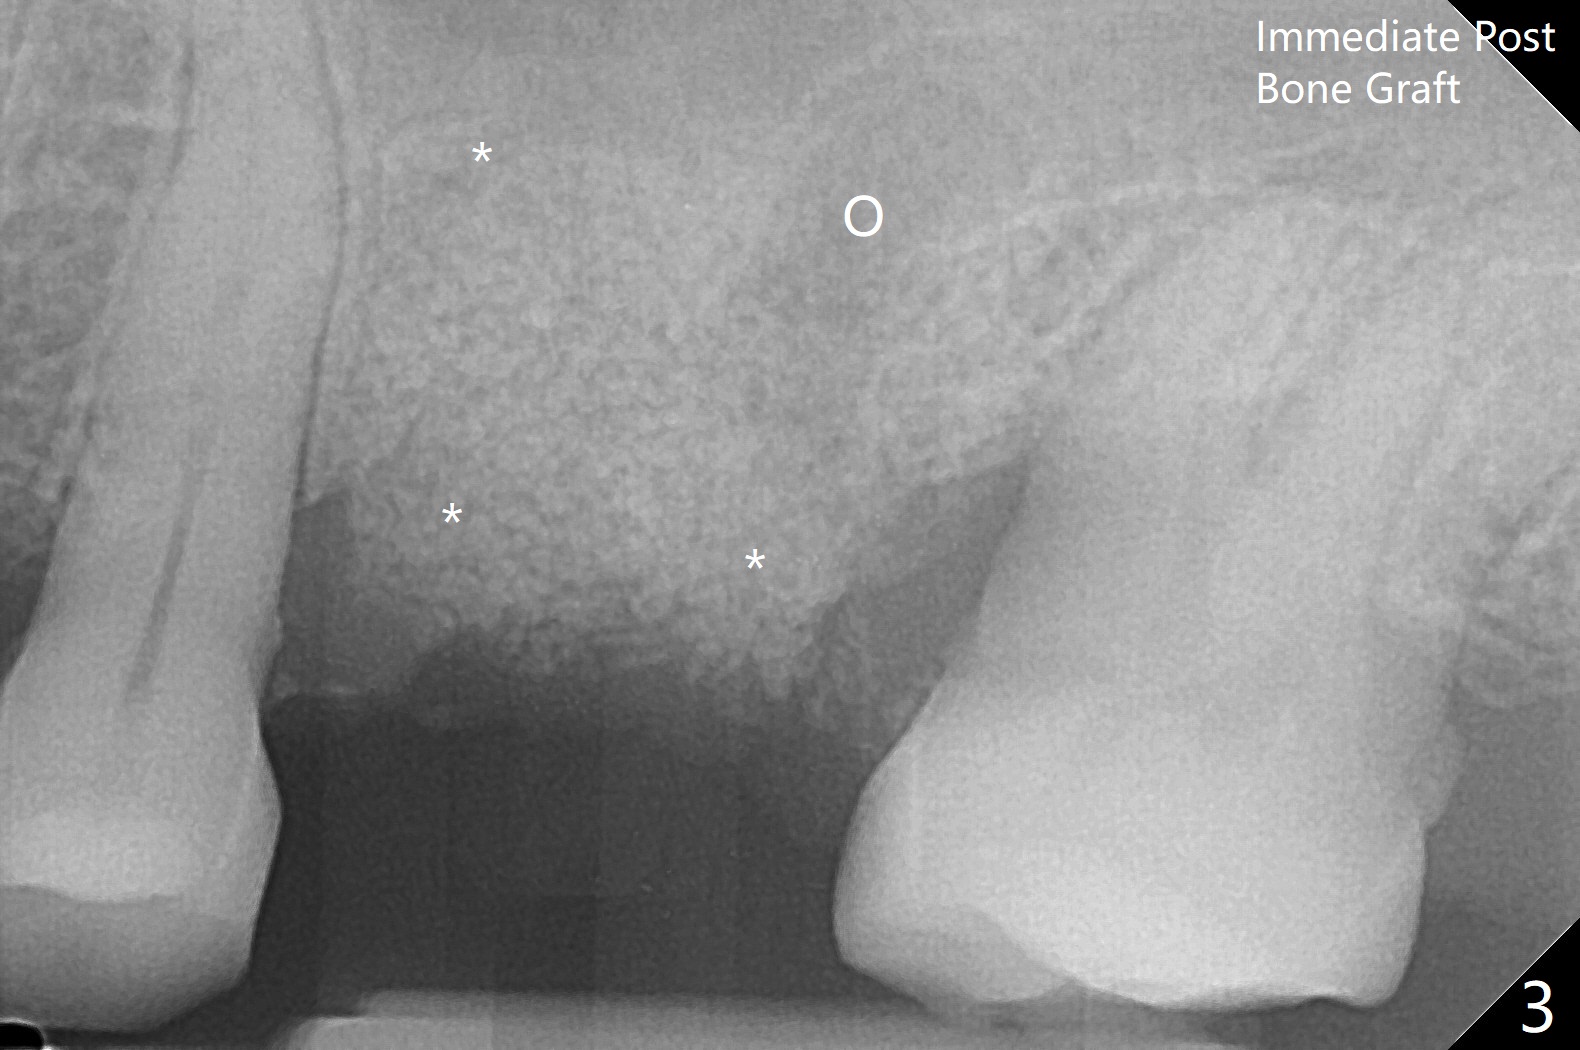

67岁女深洗后突然回来要求拔除左上六(图一),颊侧红肿,流脓,牙周袋深(图二B),经过多番劝导,终于图一植骨,由于时间仓促,使用合成血小板生长因子(GEM21S,而不是PRF))与皮质骨(125μm – 850μm)以及皮松质骨(500μm – 1,000μm)调拌,放置于巨大吸收融合颊侧牙槽窝(图三*(无颊侧骨板)(使用condenser)),而腭侧牙槽窝没有明显破坏(图一P),放置Osteogen Plug(一种骨胶原, 图三 O)。牙槽窝口放置胎盘膜(BioXclude),使用4/0 PGA缝线。傍晚病人已经 没有肿痛了。术后十三天牙周敷料脱落,伤口愈合良好。三天后病人又回来复诊(图四),折线后,虽然伤口愈合,骨粉好像填的不够多(图五),或者丢失。树脂敷料可能取得更好的结果。